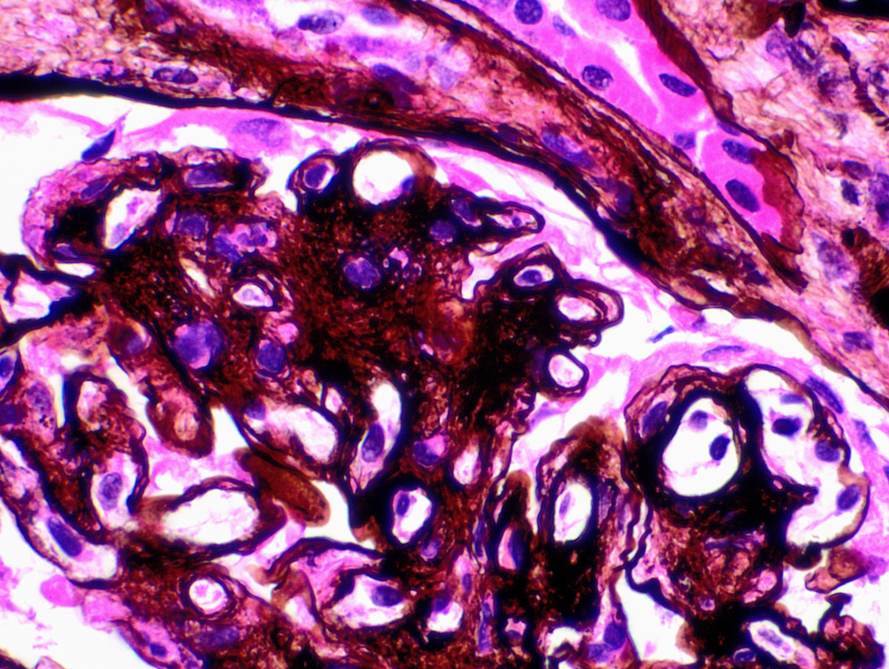

A 79-year old woman with a history of hypertension and colon cancer (1989), s/p sigmoid colectomy, presented with acute renal failure and proteinuria. All serologic workup was negative. IFE showed IgM kappa. Renal biopsy showed membranoproliferative (MPGN) pattern of glomerular injury by light microscopy (H&E Fig a & b). Immunofluorescence was negative. Electron microscopy showed glomerular basement membrane with expanded lamina rara interna and neomembrane formation (Fig c).

The ultrastructural finding of expanded lamina rara interna and neomembrane formation are the result of chronic endothelial cell injury and are c/w chronic thrombotic microangiopathy (TMA), regardless of the etiology. These ultrastructural features causes splitting of the glomerular basement membrane by light microscopy, a feature of MPGN characteristically seen in immune complex mediated diseases. A negative immunofluorescence differentiates chronic endothelial injury (TMA) from immune complex mediated process. Podocyte injury morphologically represents as an extensive foot process effacement, e.g., minimal change disease (MCD). Alport shows splitting and fraying of the lamina densa rather than expansion of lamina rara interna. Finally, resorbed deposits create intramembranous lucent defects, not expansion in lamina rara interna, typically seen in membranous glomerulopathy.